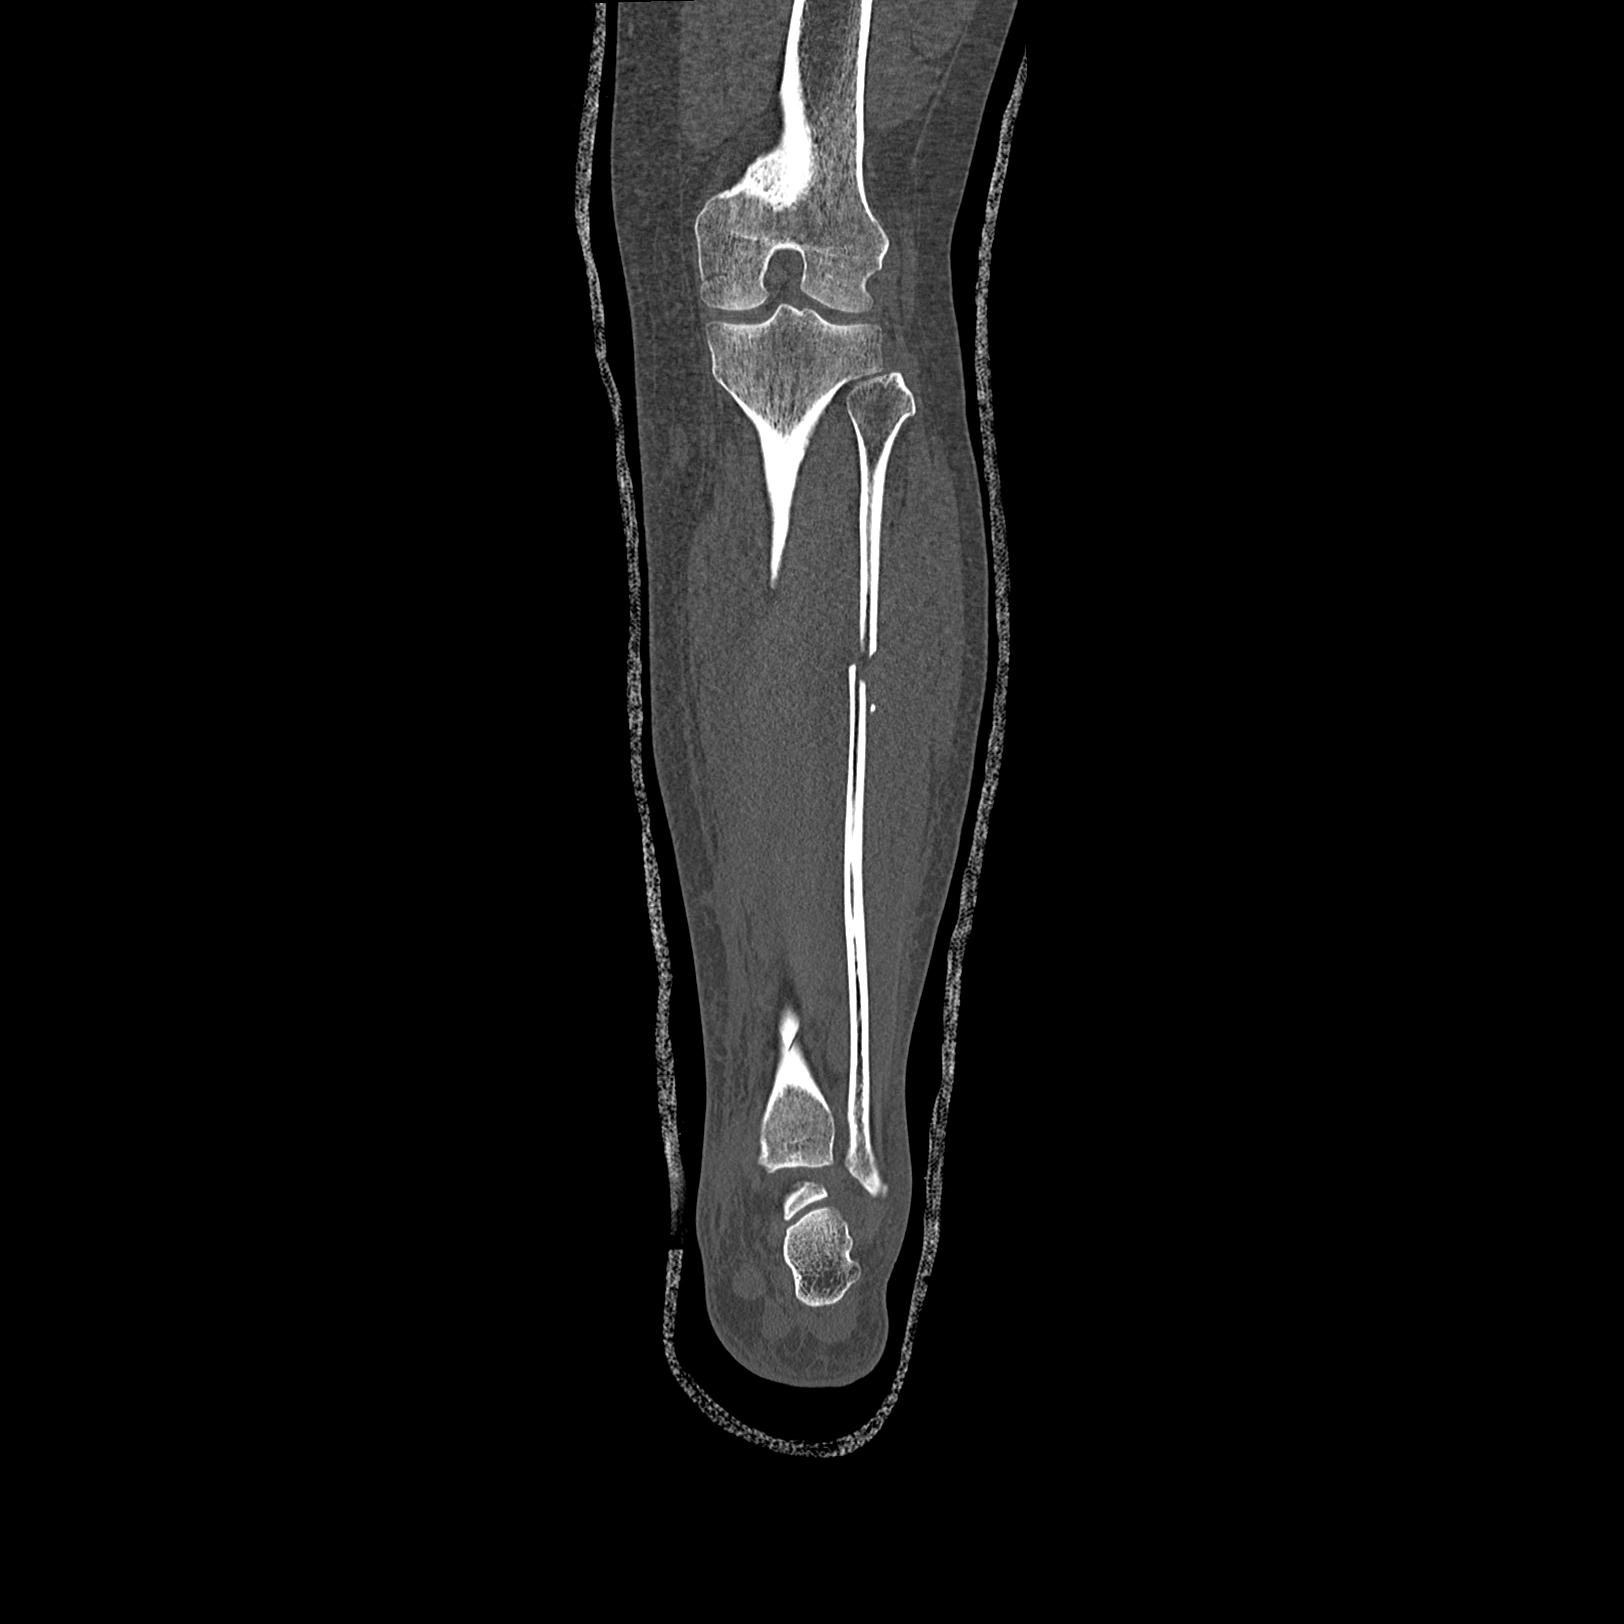

102803 1/12(キウスなし) 1/27 左下腿 4R 30歳女性 左脛骨軸内釘